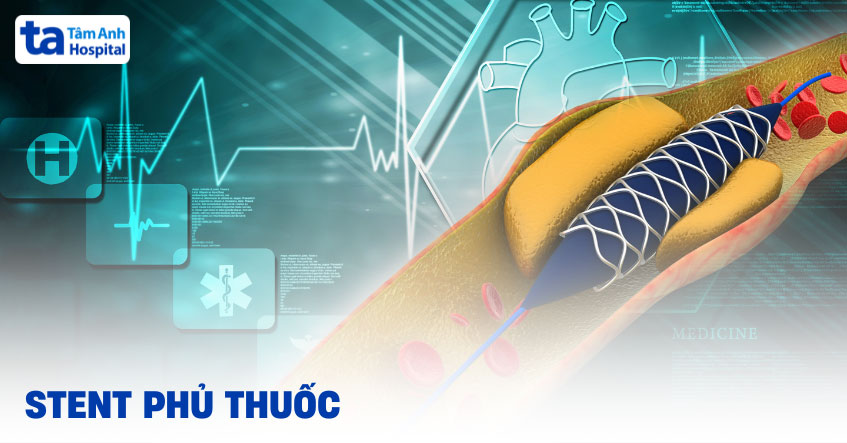

Điều trị bệnh lý động mạch vành thông qua cấy ghép stent là bước tiến lớn trong y học, mang lại nhiều lợi ích trong việc cải thiện lưu thông máu và ngăn ngừa nguy cơ tái hẹp. Trong đó, stent phủ thuốc có nhiều ưu điểm vượt trội nhờ được bao phủ bởi một lớp thuốc giải phóng chậm, giúp ngăn ngừa cục máu đông hình thành trong stent. Vậy loại stent này có vai trò gì trong điều trị bệnh tim mạch? Được dùng cho ai? Hãy cùng tìm hiểu chi tiết qua bài viết dưới đây.

Stent phủ thuốc hay DES (Drug-Eluting Stent) là một ống lưới kim loại nhỏ được đặt vào bên trong động mạch vành bị tắc nghẽn. Khác với stent thông thường, loại stent này được phủ một lớp thuốc đặc biệt có khả năng giải phóng từ từ vào thành mạch, giúp ngăn ngừa nguy cơ tái hẹp sau can thiệp.

Việc đặt stent được phủ thuốc không chỉ giúp tái thông dòng chảy máu trong lòng mạch, mà còn giảm nguy cơ tái hẹp và hạn chế hình thành cục máu đông, từ đó nâng cao hiệu quả điều trị lâu dài cho người bệnh.

Stent giải phóng thuốc (Drug-Eluting Stent – DES) không chỉ hiệu quả trong tái thông mạch máu bị hẹp, mà còn giải phóng dần thuốc chống tăng sinh tế bào, từ đó giúp ngăn chặn sự hình thành mô xơ – nguyên nhân chính gây tái hẹp sau can thiệp.